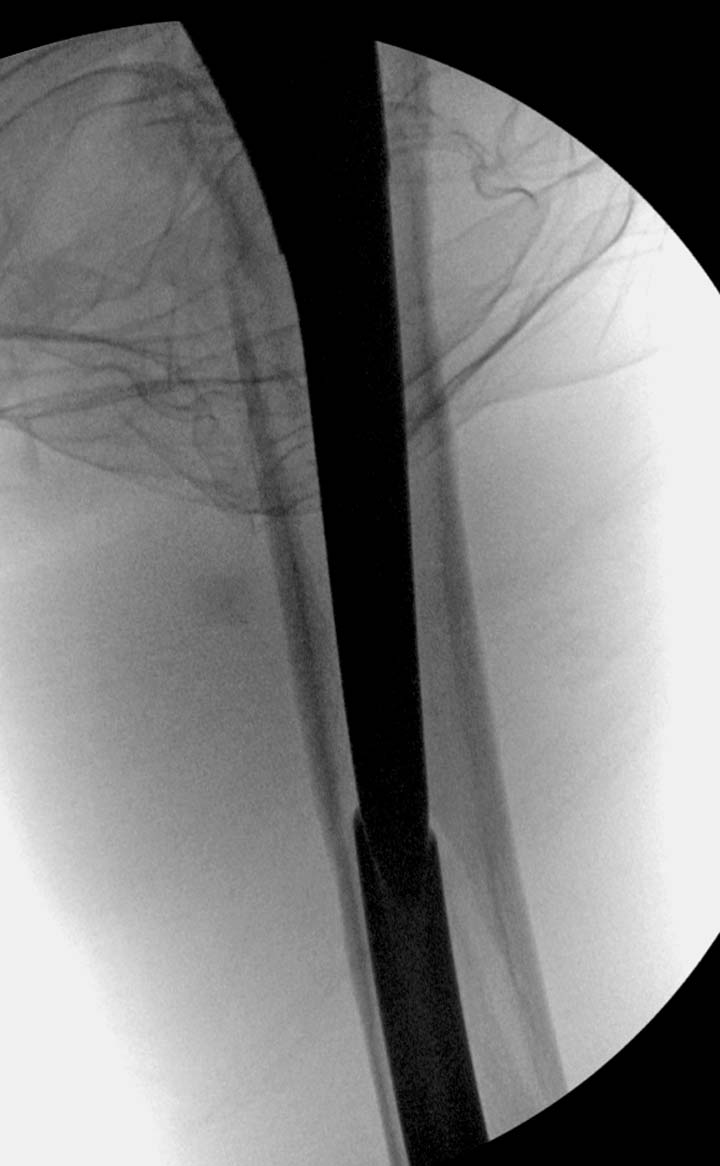

остаться до конца лечения, начал изучать язык... Для облегчения

транспортировки на второй день после поступления правая сторона была

фиксирована ретроградным гвоздем.

Теперь по серьезному. Учитывая качество кости и низкий гемоглобин,

периодический гемодиализ и воодушевленный результатом выступлении

Челнокова, вместо пластины решил попробовать гвоздь. Но жесткие FDА

Гвоздь из ретроградного гвоздя DePuy в 15 мм получился немного тоньше,

чем у Российских коллег.

Операция не обошлась без казуса, при подготовке гвоздя произошла ошибка

в расчете. Пришлось коррегигировать по ходу операции, где длинный

дистальный отдел гвоздя срезали во время операции.

А так вроде первый американский опыт прошел удачно. У больного низкий

гемоглобин, который подправили во время операции переливанием крови.

надеюсь, контрагированные мышцы сохранит длину конечности. Контрольный

снимок показал устойчивую фиксацию.